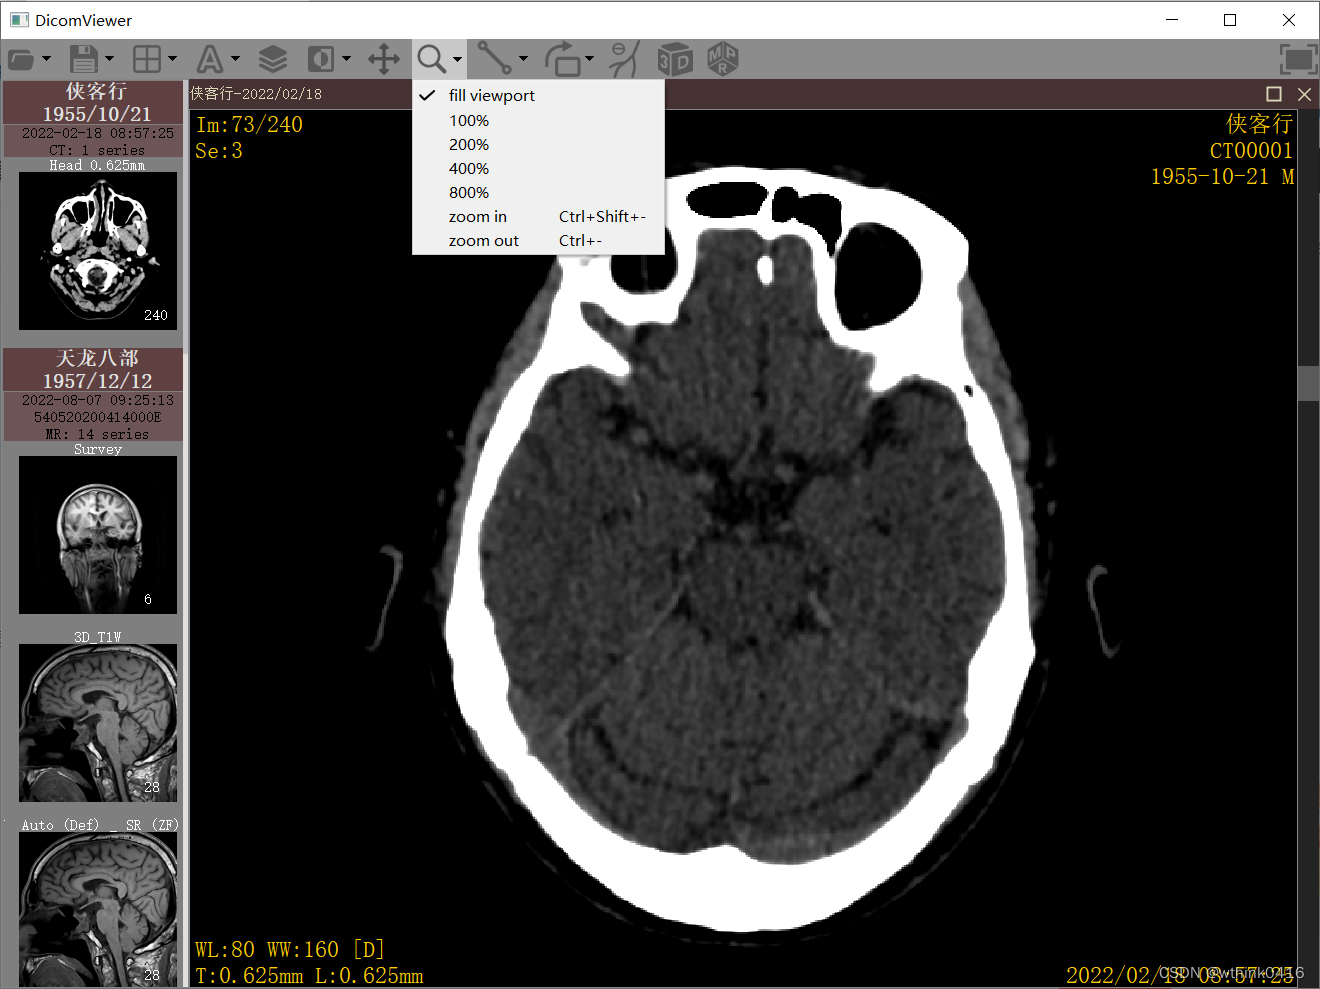

7、点击![]() 缩放图标后,鼠标左键按下同时移动,可实现快速缩放,下拉菜单支持一些预设缩放比例。

缩放图标后,鼠标左键按下同时移动,可实现快速缩放,下拉菜单支持一些预设缩放比例。